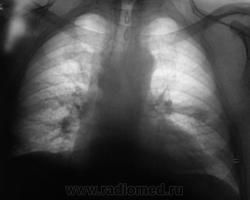

Начало 2008 года. При расшифровке флюорограмм, пациента "взяли на контроль", заподозрили периферический рак левого лёгкого (по "прямой" флюорограмме). Вроде-бы все правильно и логично?

В апреле 2009 года пациент пришел "для динамического наблюдения" - серия 2.

После повторного дообследования (апрель 2009 г) - 2 серия изображений, мы были твердо уверены, что пациент взят на учет..., но не тут-то было. В пятницу рентгенолаборант флюорографа попросил подойти и "глянуть снимок"...

Оказывается "данный" пациент направлен для прохождения профилактической флюорографии..., так как надо было поменять водительские права...?

Вот флюорограммы.

2. Конечно, мы на свой страх и риск, произвели дообследование, согласно стандарту. Итог дообследования представлен в серии 3.